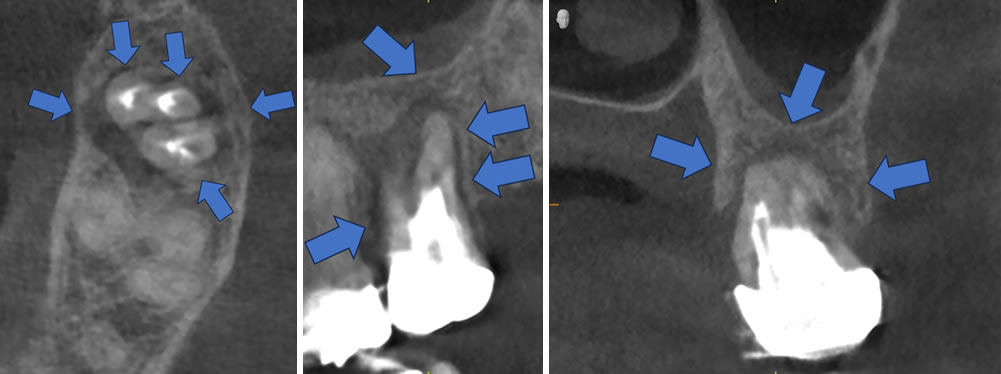

治療から約1年半後のレントゲン写真・CT画像

しかし、CT撮影してみると先ほどのレントゲンよりも黒い影(顎の骨が吸収している)の範囲が広かったことが確認できました。

ですが、幸い手前の歯までは広がっておらず、歯を支えている顎の骨も何とか維持できている(青矢印)ので、その点はかろうじて及第点かと思います(抜歯を回避して1年半経過したという意味で)。

とはいえ、今後この顎の骨が吸収している範囲が広がっていかないか?日常生活に支障が出るような症状が再び出てこないか?はやはり心配ですので、引き続き要観察だと考えております。